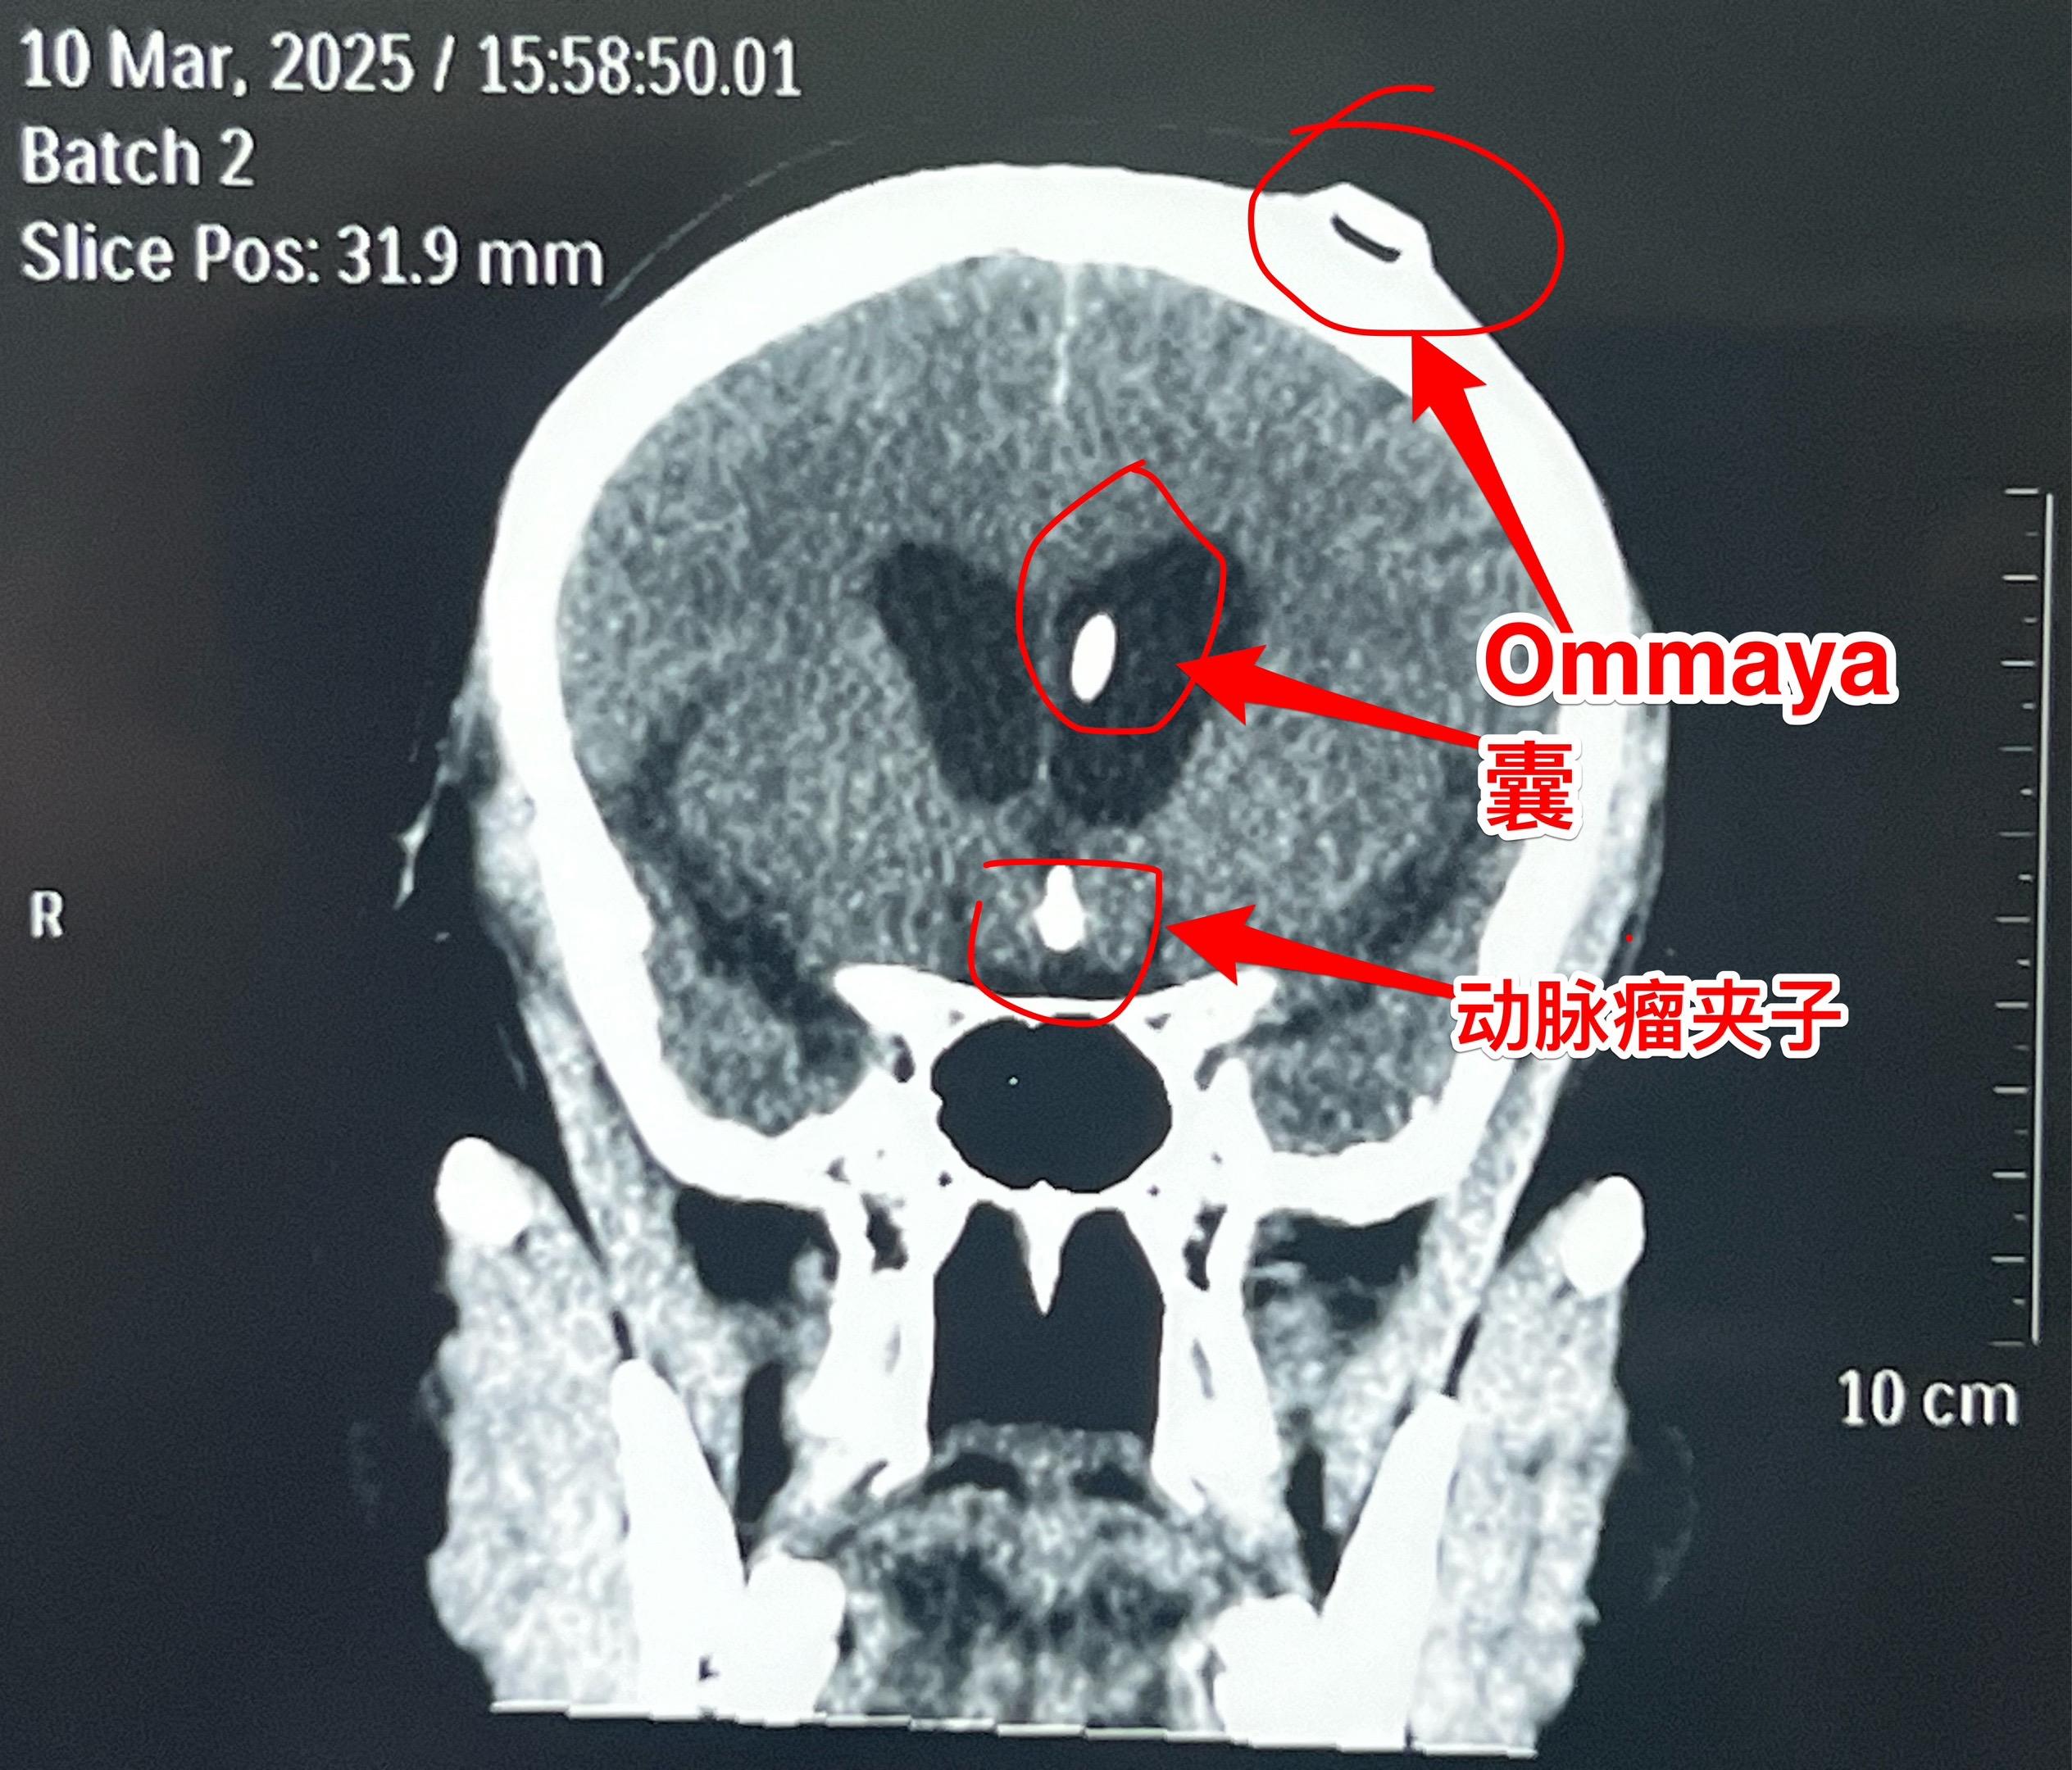

乳头型和造釉型颅咽管瘤的混合型存在吗?34岁男性,广东省惠州市人。一年前因视力下降发现颅咽管瘤,在广东省某医院行开颅手术切除一部分肿瘤。肿瘤复发了来三博脑科医院找我治疗。 第一次手术后病理报告考虑是乳头型颅咽管瘤和造釉型颅咽管瘤的混合型(太罕见了)。手术中还留置了一个动脉瘤夹子、一个Ommaya囊。 昨日作了开颅手术,术中看见肿瘤血供十分丰富,和第三脑室壁及大脑后动脉粘连。手术经历9.5个小时,肿瘤得到完全切除。术后病人的精神状态及四肢活动均很好。希望以后肿瘤不复发。等待病理